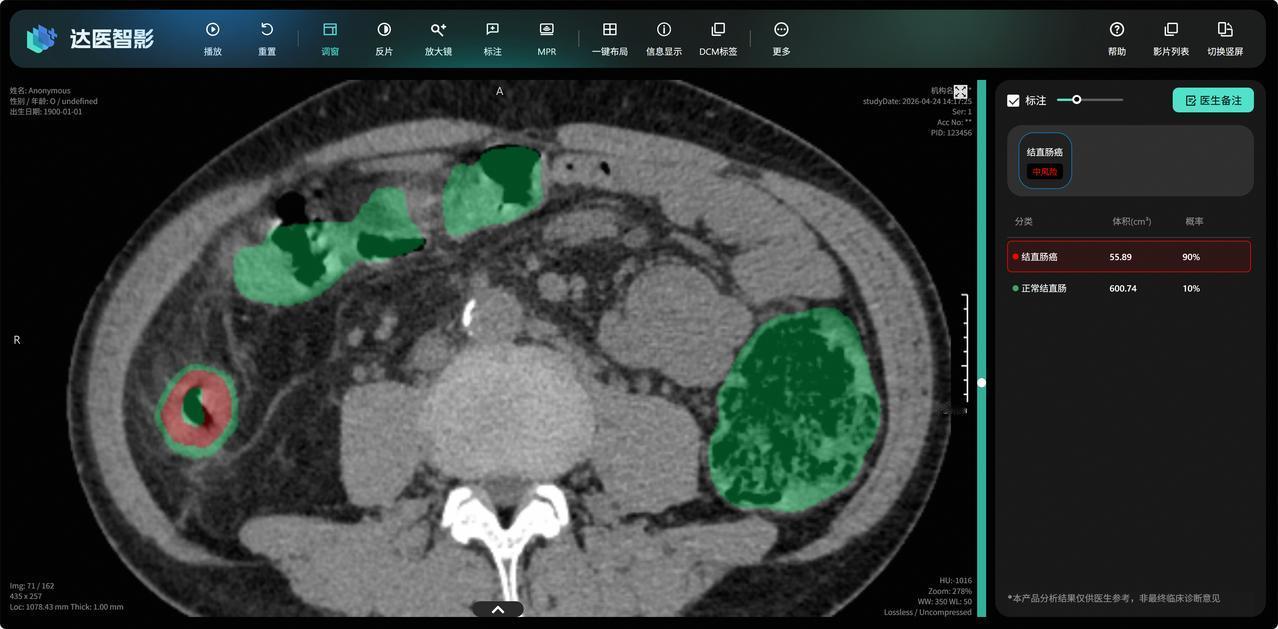

现在社会上有一个明显变化,很多人都意识到了,已经改变了很多人的命运! 不知道大家发现了没有,现在大家的健康意识越来越强了,通过身体的一些变化,很多网友都能判断到身体可能有问题。比如最近陆毅嘴唇发紫,就被很多网友建议去看看医生,陆毅还真听劝去检查了心脏各方面的指标。 很显然,大家对于身体健康越来越重视了,但现实生活的经验告诉我们,有的病通过身体的一些表面变化能感受到,但像癌症这种生命杀手,却非常的阴险,藏的很深。 想要解决这个问题,最好的办法就是去做癌症筛查,而在这方面,咱们的科技公司已经又向前迈出了重要的一步。 最近看到新闻,阿里达摩院通过AI进行癌症筛查的技术,又实现了突破。根据报道,阿里达摩院联合广东省人民医院等机构研发出肠癌筛查AI模型DAMO COCA。 这个模型已经从2.7万人的平扫CT影像中精准识别5例漏诊肠癌。其敏感性、特异性分别达到86.6%和99.8%,放眼国际,这种水平也是顶尖的存在。 除了精度特别高,该技术还是国际上首次提出的一种无需肠道准备、简便高效的肠癌“无感”筛查方法。这项研究的论文还登上国际顶刊《肿瘤学年鉴》(AnnalsofOncology),这是最权威的肿瘤学原创期刊。 技术含金量毋庸置疑,关键是价格非常低。 这项技术最重要的一个核心逻辑是,通过AI+CT平扫的方式,就能实现癌症筛查。也就是说过去做一次癌症筛查花几千上万,现在做一次200元的CT平扫,就能做癌症筛查,这也真正做到了技术普惠。 除了这次在肠癌的癌症筛查方面取得了突破性的进展,此前阿里达摩院的AI,还在胰腺癌、胃癌等癌症筛查方面取得了突破,都登上了国际顶级期刊,而且已经在多个医院部署,发现了很多医生没发现的潜在癌症。 癌症筛查,对于不幸患病的病人来说,是能救命的。很多癌症的患者为啥一发现之后就不行了?主要还是发现的晚,等有了症状之后才去的医院。数据也显示,早期肠癌5年生存率超90%,晚期不足15%。 所以从这方面来看的话,阿里达摩院的癌症筛查AI模型,是有重大现实意义的,他让每一个普通人都能用得起,做得上癌症筛查,既降低了筛查费用,也能揪出癌症这个隐藏的杀手,也希望阿里达摩院能在这方面继续进步,推出更多医疗模型来提升普通人的生活幸福感。